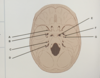

what is A

foramen retundum

what is B

foramen ovale

what is C

IAM

what is D

jugular foramen

what is E

foramen lacerum

what is F

foramen spinosum

what is G

carotid canal